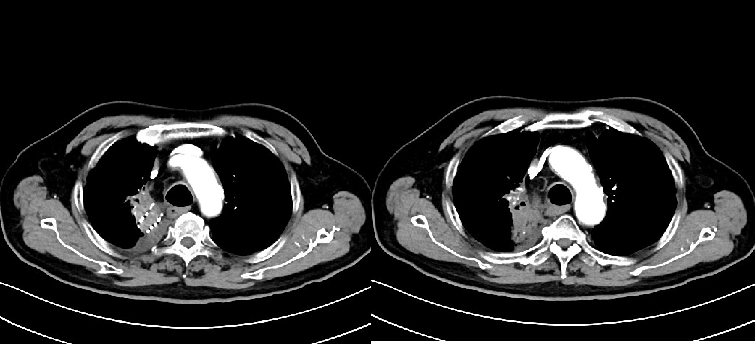

2023年9月16日,患者因气喘,复查胸腹部增强CT(图5):符合右肺上叶病变粒子植入表现、符合右肺下叶及左肺上叶纤维灶、结节灶,邻近支气管扩张、COPD,左侧肾上腺结节。痰培养:铜绿假单胞菌。后多次因肺炎给予抗炎治疗。

2024年4月,查胸部强化CT(图7):符合右肺上叶病变粒子植入表现,较前略增大;符合右肺下叶及左肺上叶纤维灶、结节灶,邻近支气管扩张;COPD、右侧胸腔积液、左侧肾上腺结节较前大致相仿。患者家属拒绝再次活检及静脉化疗。

经MDT会诊,给予 “长春瑞滨软胶囊40mg tiw+重组人血管内皮抑制素210mg civ72h”治疗。5周期,影像学检查右肺肿瘤缩小,患者无胃肠道反应(图8),血常规检测无骨髓抑制(图9)。

2024年9月7日,复查胸部CT(图11):1.符合右肺上叶癌粒子植入表现。2.符合左肺上叶纤维灶、结节灶,邻近支气管扩张复查表现。3.右下肺纤维灶。4.符合COPD影像表现。5.左侧肾上腺结节。

2024年12月,患者因腰痛来院,查CT(图12):右肺上叶癌粒子植入表现,左肺上叶转移治疗期表现,COPD并左肺下叶纤维灶,左侧肾上腺结节较前未见变化,T11椎体及左侧附件、骶1-2椎体骨质破坏,考虑转移瘤。

2025年1月,给予“长春瑞滨软胶囊40mg tiw+卡度尼利625mg d1+重组人血管内皮抑制素210mg CIV72h”治疗2周期,无胃肠道反应及骨髓抑制(图13)。